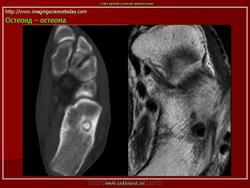

При рентгенологическом исследовании остеоид-остеома обнаруживается как субкортикально расположенный участок окостенения, окруженный ободком остеосклероза, ширина которого увеличивается по мере прогрессирования опухоли. При этом центральная часть опухоли становится менее заметно. Граница между центральной светлой зоной и склеротическим ободком, отчетливая в ранний период, со временем стирается вследствие того, что центральная зона опухоли подвергается оссификации и обызвествлению, которые распространяются центробежно. Рост кортикальных и субпериостальных остеоид-остеом сопровождается также реактивным склерозом- Имеются указания и на то, что если новообразование растет в костномозговом канале, то в соответствующей кости развивается остеопороз. Обычно опухоль легко вылущивается из окружающей кости и макроскопически представляет собой мелкозернистую, красновато-бурую костную ткань. Остеоидную остеому, как правило, удаляют хирургическим путем. Рецидив возможен, но практически не встречаются. Если он и происходит, то спустя 10 лет и позднее после удаления первичного узла опухоли.

Рентгенологическая картина. На обзорных рентгенограммах очаг поражения характеризуется утолщением и уплотнением кортикального слоя кости вокруг небольшого литического гнезда.